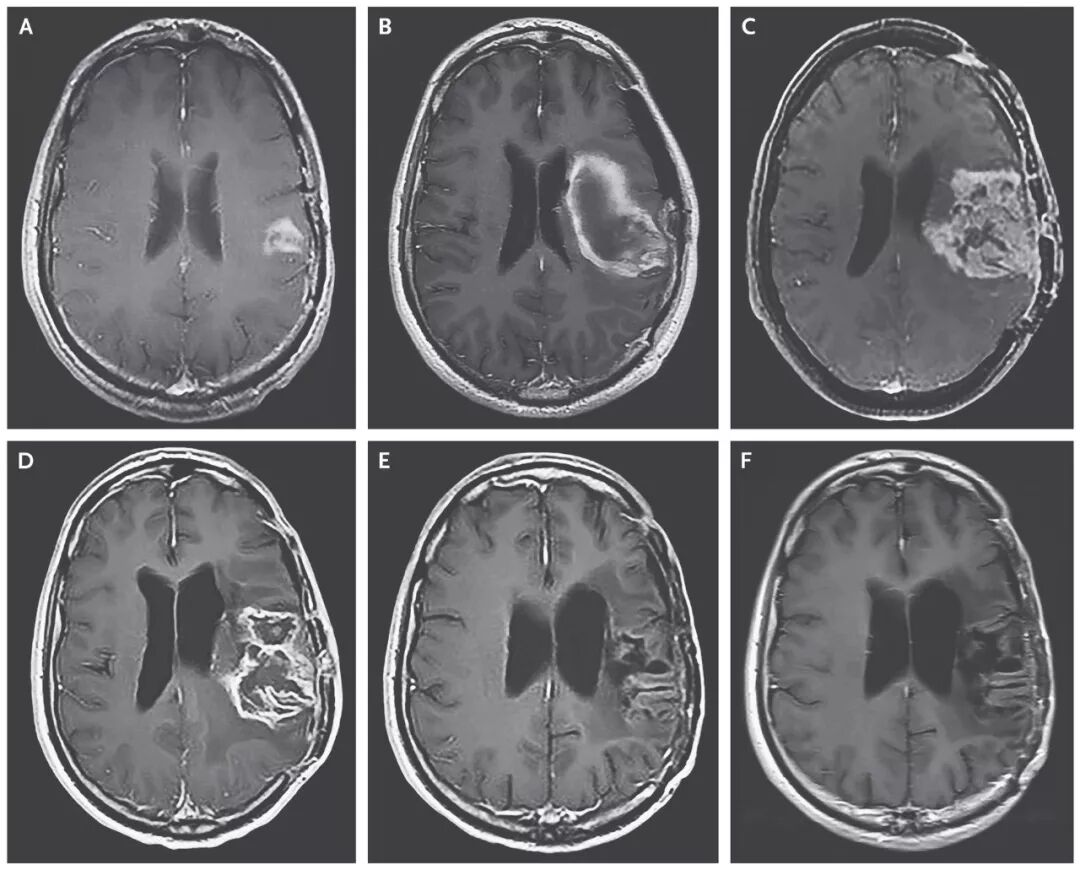

溶瘤病毒创造恶性脑瘤完全缓解的治疗奇迹!

截止2018年3月20日,8名患者对治疗产生治疗应答,2名患者的脑胶质瘤病灶完全消失,达到了完全缓解!

▲患者脑部肿瘤的缩小清晰可见(图片来源:《NEJM》)

这位患者,经过PVSRIPO溶瘤病毒治疗7个月后,病情复发后使用洛莫司汀治疗,经过12个月的洛莫司汀治疗后,病人的病灶完全消失并保持了20个月的无病状态,并且在PVSRIPO溶瘤病毒治疗发生出血后57.5个月仍然存活。